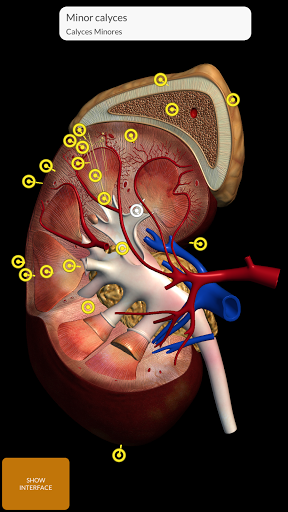

"Anatomy 3D Atlas" memungkinkan Anda mempelajari anatomi manusia dengan cara yang mudah dan interaktif.

Melalui antarmuka yang sederhana dan intuitif, Anda dapat mengamati setiap struktur anatomi dari sudut mana pun.

Model 3D anatomi sangat terperinci dan memiliki tekstur hingga resolusi 4k.

MODEL ANATOMI 3D